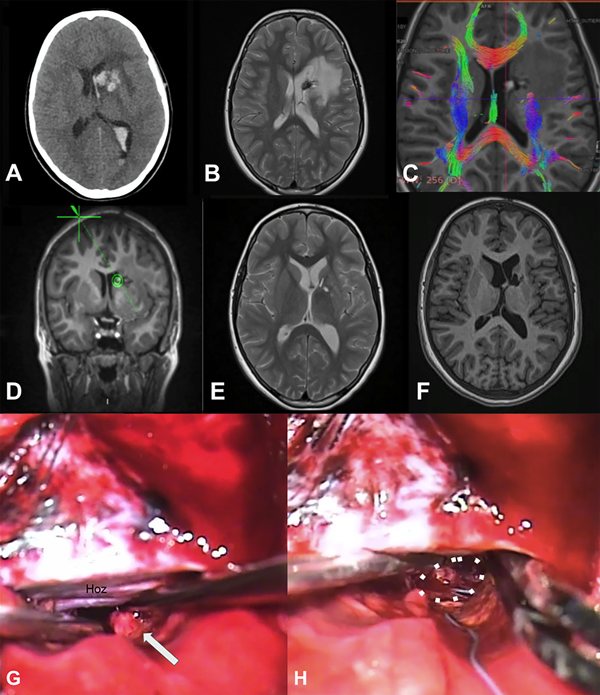

Figura 2. Cavernoma cerebral supratentorial profundo, ubicado en la cabeza del núcleo caudado izquierdo. Paciente femenina de 10 años que ingresa por síndrome de hipertensión endocraneana y primer episodio de sangrado con volcado intraventricular A) requiriendo colocación de drenaje ventricular externo. Evolucionó favorablemente. B) RM cerebral secuencia T2, paciente reingresa a los 2 meses por nuevo sangrado, agregando hemiparesia crural derecha, se decide cirugía programada. C) RM secuencia DTI-tractografía, realizada para planificación quirúrgica. D) RM cerebral, planificación quirúrgica mediante neuronavegación, eligiendo un abordaje transcalloso contralateral. E) y F) RM secuencias T2 y T1 en el postoperatorio, muestran la resección completa. G) y H) Imágenes microquirúrgicas. Se observa la hoz del cerebro y el cavernoma disecado (flecha blanca), en la línea de puntos blanca se observa el lecho quirúrgico con restos de hemosiderina.